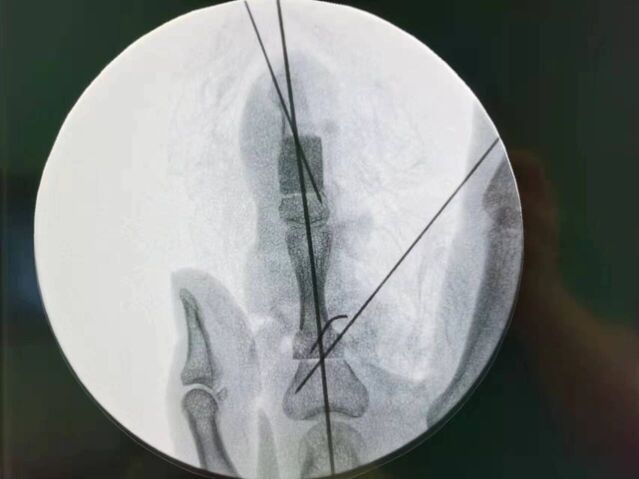

今天的环指再造

微信图片_20231008195909.jpg 微信图片_20231008195912.jpg 微信图片_20231008195906.jpg 微信图片_20231008195903.jpg 微信图片_20231008195839.jpg 微信图片_20231008195829.jpg 微信图片_20231008195945.jpg 微信图片_20231008195939.jpg